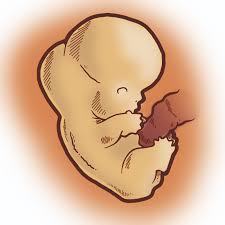

Semana 8 de embarazo. Uno de los hechos más importantes es que se empiezan a visualizar los rasgos faciales del embrión tales como la forma de la nariz el labio superior las orejas y los párpados. El bebé de 8 semanas de embarazo tiene el tamaño de una frambuesa es decir imagínate es tan diminuto que su tamaño es como la de una bola de goma de mascar. Ya deberías haber contactado con tu obstetra.

Además pesa cerca de 025 g y mide aproximadamente entre 7 y 17 mm más o menos media pulgada. En la semana 8 se empieza a formar la piel del embrión que es translúcida y. Riesgo de aborto en la semana 8 de embarazo.

Al final de esta octava semana de embarazo todos los sistemas y órganos importantes estarán formados aunque algunos estén en fases iniciales de desarrollo. El embrión crece a un ritmo trepidante.